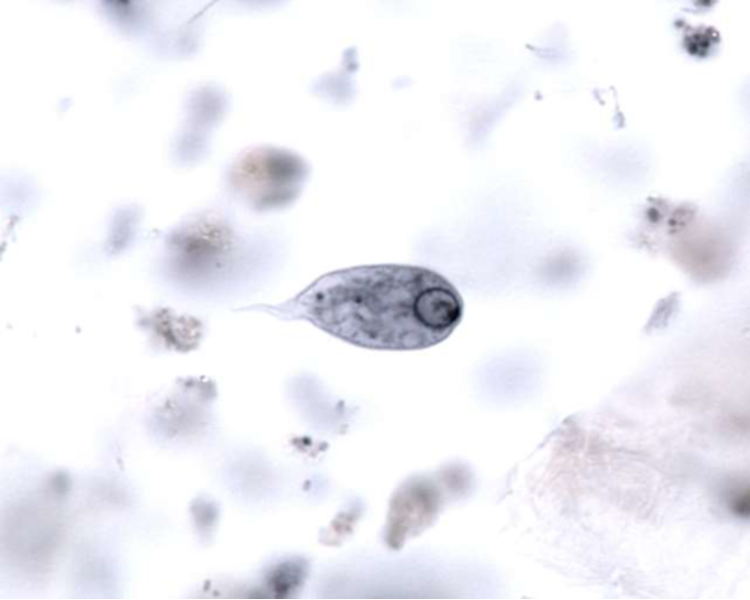

cyst wall (from: cystoisospora belli oocyst)

sporocyst?

cystoisospora belli oocyst